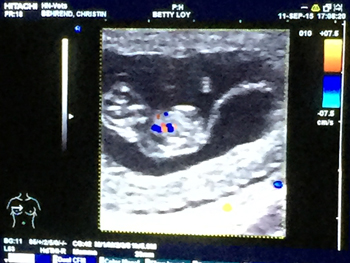

Heute, am

11.September waren wir beim Ultraschall,

und wir haben richtig geraten....

jippi - Lou bekommt Babys !

Hier zwei Bilder, wo man schon ganz genau

ein kleines heranwachsenden Dalmatinerbaby sehen kann

Es werden aber sicher mehr, als nur eins ;-)